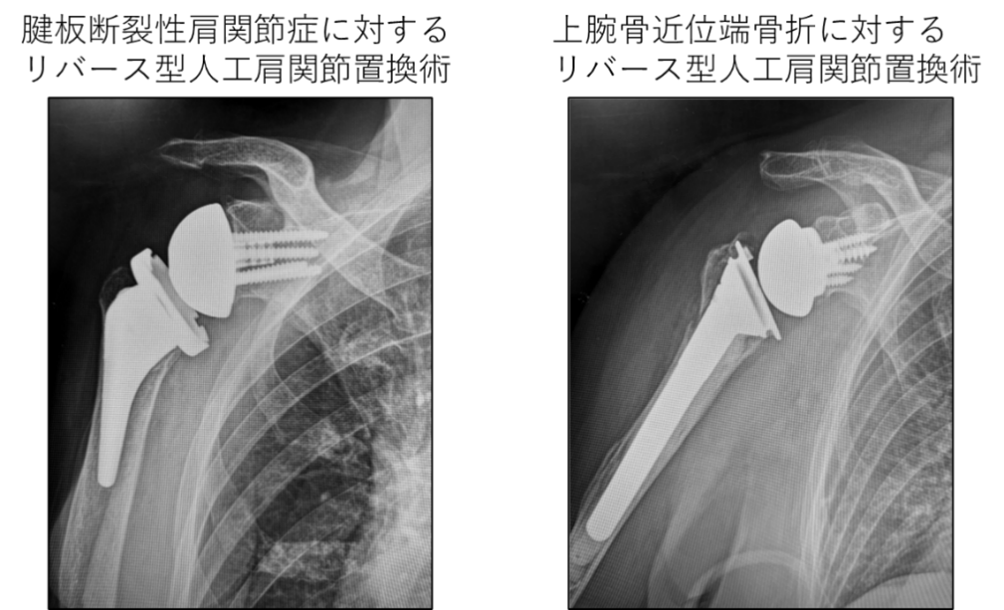

- ●変形性肩関節症、腱板断裂性肩関節症などにおいては、病態に応じて人工骨頭挿入術、解剖学的人工肩関節置換術、2014年より本邦でも使用可能になったリバース型人工肩関節置換術を施行しております。

- ●上腕骨近位端骨折においては、骨折型に応じて保存療法、髄内釘、プレート固定、人工関節置換術を施行しています。